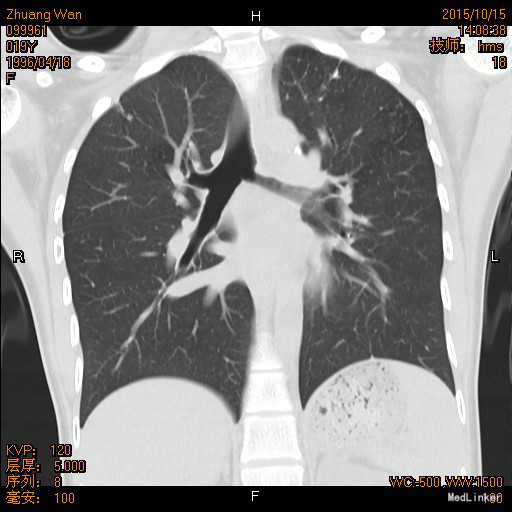

年轻女性患者,9月余前自觉呼吸时气管里发出声音,为持续性,查支气管镜检查确诊为左主支气管狭窄。先后曾于外院及我院共行球囊扩张5次,治疗后上述症状消失。现患者返院复查来我科。既往左上肺结核病史1年余,目前口服异福胶囊、乙胺丁醇治疗。

查体:双侧胸廓不对称,未见明显畸形,左肺上叶呼吸音弱。 辅查: 胸部CT:双肺上叶结节影,考虑结核可能性较大;左侧支气管狭窄。

诊断:左主支气管狭窄 双侧肺结核 治疗: 排除禁忌症后,在呼吸内镜室行支气管镜下气囊扩张术,嘱术后坚持规律服用抗结核药物,不可自行停药,定期复查血常规、血沉、肝肾功能,至当地结核病防治所随诊。

年轻患者单侧支气管狭窄,易误诊为先天性疾病,然而应排除肺部占位性病变。该例狭窄继发于肺结核,为瘢痕形成,在抗结核治疗的基础上,物理扩张十分必要。